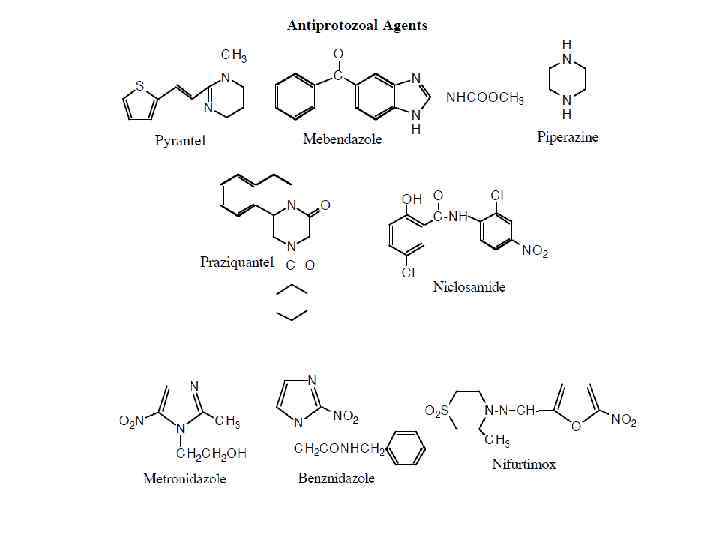

В случае, если тестируются фармакологические противопаразитарные препараты (вермокс, немазол, пирантел, празиквантел, вормин, левамизол), их можно комбинировать с молибденом, реже – с аргинином. Следует помнить также о сочетаниях перечисленных препаратов с травами (порошки, настойки, отвары). Применение прочих препаратов зависит от сопутствующих клинических состояний. © И. Г. Бондаренко, 2011